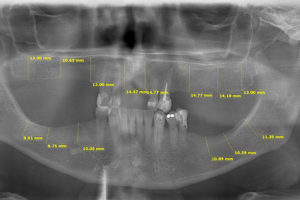

MEDICIONES PARA PRÓTESIS E IMPLANTES DENTALES

Este procedimiento se lo realiza sobre la radiografía panorámica, de senos maxilares y tomografía 3D, nuestro moderno software permite tener una medición exacta de rebordes maxilares, información requerida para colocación de prótesis e implantes.